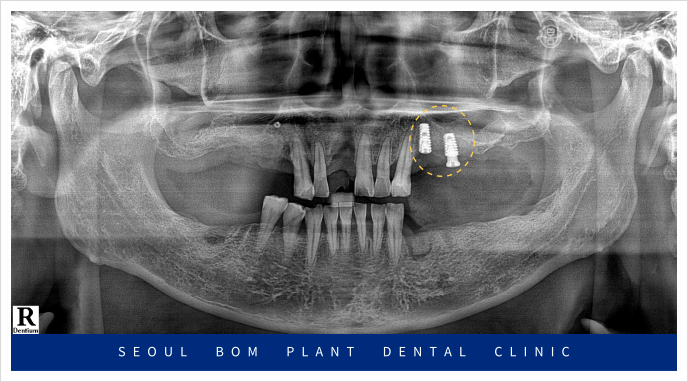

먼저 왼쪽 위턱의

기존 상실된 부위부터

임플란트 식립을 진행하였으며

잇몸이 아무는 정도에 따라

아래턱 오른쪽과 왼쪽에 차례대로

임플란트 식립을 진행하였는데요.

발치를 했던 부위이다 보니

잔존 치조골의 양이 부족하여

잇몸뼈를 충분히 보완한 뒤

안정적으로 임플란트 식립을

도와드렸습니다.

위턱의 오른쪽 임플란트도 진행하였는데요.

위턱 오른쪽 어금니 부위의 경우

잔존 치조골과 상악동과의 거리가

가깝게 위치해 있어

임플란트를 식립하기에는

수직적인 거리가 부족하여

이 경우 상악동 거상술을 동반한

뼈이식이 필요하였는데요.